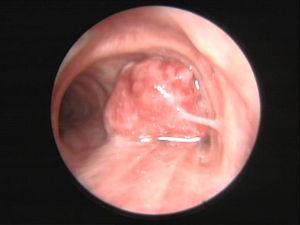

Chest X-ray showed a heterogeneous opacity in the right lower lobe with an ipsilateral mediastinum deviation. The patient was started on antibiotics as community acquired pneumonia was initially assumed. Because there was neither clinical nor radiological improvement after 5 days of treatment, a chest computed tomography scan was performed showing obliteration of right main bronchus and consolidation of right inferior and middle lobes. Flexible bronchoscopy revealed a 2 cm pedunculated, glossy and lobulated lesion with implantation base on the right upper lobe carina, totally obstructing the right main bronchus and protruding to the trachea (Figure 1). As rigid bronchoscopy was readily available it was then performed and the lesion was fully removed at once with a biopsy forceps. Nd-YAG LASER was applied to the base of the lesion. The patient was discharged after 2 days, asymptomatic and with a normal chest X-ray. Histological examination revealed a respiratory epithelium with focal Malpighi metaplasia, with an axis containing many congested and dilated vessels, surrounded by stroma with variable collagenization, and lymphoplasmocytic inflammatory infiltrate accompanied by several mast cells, which established the diagnosis of a fibroepithelial polyp (Figure 2).

Figure 1. A 2 cm pedunculated, glossy and lobulated bronchial fibroepithelial polyp obliterating the right main bronchus.